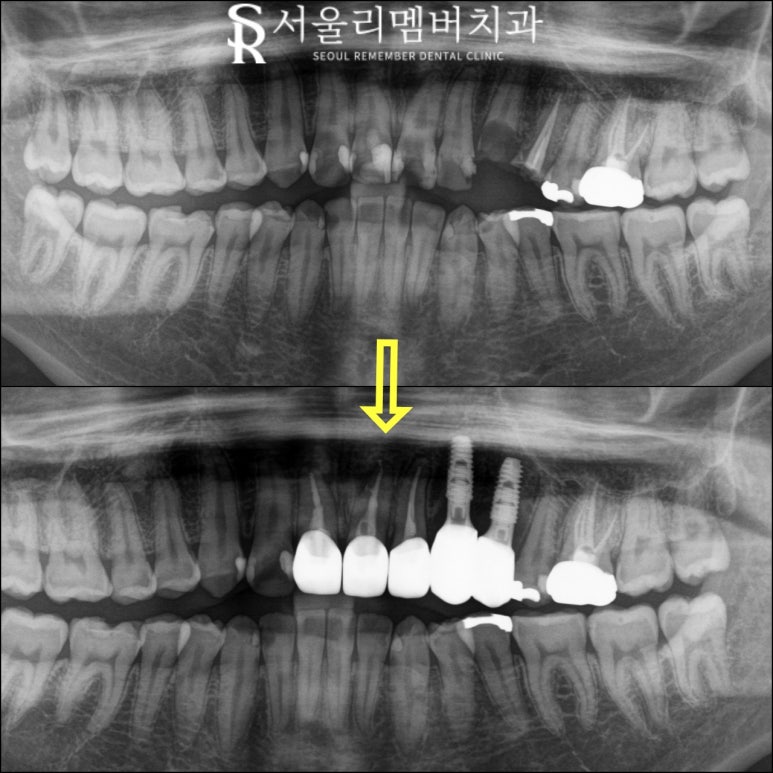

전후 사진으로 보여 드리겠습니다.

x-ray를 먼저 보겠습니다.

부러지고 충치로 가득 차 있던 앞니는 보존하고

그리고 임플란트 식립한 부위는

튼튼한 치아들을 관찰할 수 있습니다.